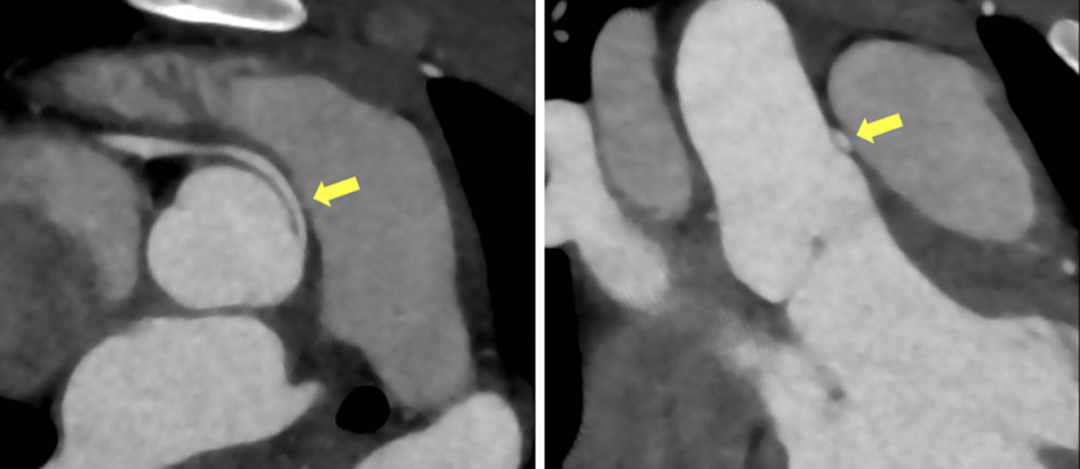

ROC曲线分析以最大化敏感性为阈值选择标准,CCTA开口部短轴(cutoff≥1.8 mm)的诊断性能最佳(AUC=0.82),敏感性为100%,NPV为100%,特异性为57%,PPV为47%。其他参数如最小管腔面积等也显示类似趋势,但开口部短轴的可重复性最高(测量者内/测量者间相关性良好)。

逻辑回归分析显示,CCTA参数中R-AAOCA最小管腔面积(OR 0.27)、最小管腔面积短轴(OR 0.002)、开口部管腔面积(OR 0.51)和开口部短轴(OR 0.01)对预测血流动力学相关性最具显著性(均P<0.01)。